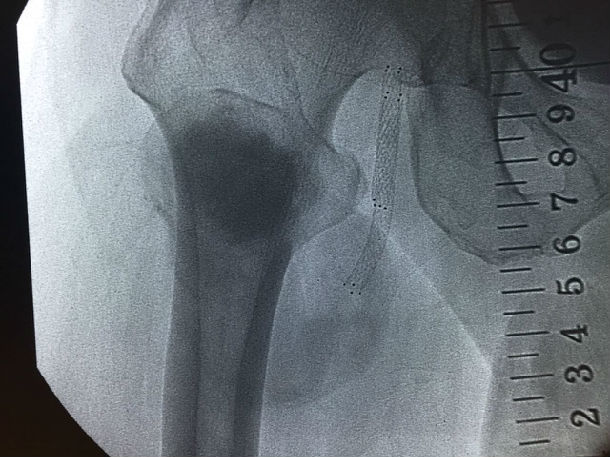

入院后查体:患者右腹股沟下1cm处可见一搏动性包块,6*9cm,边界清楚,质偏软,表面无红肿及淤血,表面皮肤完整,无破溃。

超声提示:右侧腹股沟区见假性动脉瘤形成伴附壁血栓形成,囊性包块6.5*10.3cm,与髂外动脉相同,可见红蓝相间的血流信号。

春节将至,能否给患者和医务人员的我们一个满意的答卷呢?周全的手术方案和万全的准备是必须的。看似简单的股深动脉瘤,确实是对我们技术的严峻挑战。分析病例我们不难发现该病例的一些特点:如果我们采用传统的外科手术方式是较为安全的,但是其中潜在的问题,如开刀风险、手术创面大,术后淋巴管漏等并发症较多,另外术后恢复时间较长,在这特殊时间内对患者来说并不是最好的选择。有没有更简单、经济、创伤较小的方法呢?经讨论后提出多种手术方案:最理想治疗是用小型覆膜支架封堵瘤体口,但是,根据患者下肢血管CTA提示,该患者髂动脉严重迂曲,成角偏小,右侧髂动脉迂曲成直角,入路困难,另覆膜支架顺应性差,植入困难,费用也较大,作为备选方案。如果用传统单纯的弹簧圈治疗,巨大假腔,费用大,疗效不确切,并且有可能会有远期不适,也列入备选方案。还有就是经左侧穿刺,翻山至右侧股深动脉,小球囊封闭瘤体口,经球囊向瘤体内注射凝血酶,待自身形成血栓后,释放球囊,用2枚裸支架覆盖瘤体口,这样既减少创伤,减少费用,同时可防止瘤体内血栓脱落至股深动脉,此手术方案较为理想。那么实际操作中会是怎样的结果,我们无法预知,充足的术前准备显得尤为重要。入路的选择:患者高度肥胖,股动脉穿刺困难(脂肪厚股动脉触摸困难,穿刺要求很高,一旦出问题后果不堪设想)。支架的选择,我们联系多方厂家备用所有可能会用到的支架,介入治疗失败或是操作受限后外科的手术也全部就位。2016-02-03手术在计划中进行,患者体型肥胖,股动脉触摸困难,穿刺就是一个挑战,凭我们丰富的经验,一针见血,穿刺成功通过,更严峻的挑战还在后面,置管造影显示,患者髂动脉严重迂曲,多处迂曲近直角,所有的操作都需谨慎小心,防止导管打折、断裂,引起出血,另多次在各个分支和假腔血管间选择,假腔内操作容易导致瘤体破裂,造成大出血,技术难度大。手术紧张而有序,反复确认瘤体开口口径及有无流出道后,球囊顺利送达瘤体口内,经球囊注射凝血酶,能否形成血栓,大家拭目以待。20min过去了,透视见瘤体内预先残留的造影剂不再消失,自身血栓形成,看到了成功的希望,由于患者动脉迂曲严重,翻山鞘管规格有限,覆膜支架顺应性差,鞘管支撑力不够,经各位医生讨论后,决定用2枚裸支架代替,精确定位后,顺利释放支架,复造影见支架位置良好,贴壁良好,无明显血流渗入瘤体,瘤体搏动消失。患者目前恢复良好,预计可以在春节前2天回家过年。